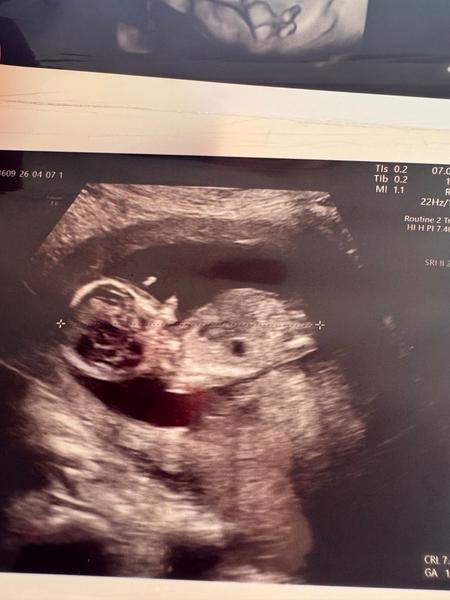

Může být ve čtrnáctém týdnu poznat pohlaví dítěte?

Ahojky,co myslíte může to být kluk nebo spíš holka?Nebo nejde to ještě poznat.Jsem 14 týdnů

@katerinaflidrova bylo by to poznat, kdybys dala fotku z profilu a muselo by tam být celé tělíčko, abychom viděli pohlavní hrbolek.

Ale z doložených fotek nelze poznat nic, protože oblast pohlavního hrbolku není zaznamenána.